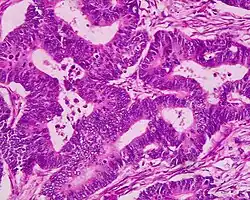

| Colorectal adenocarcinoma | 100% |

|

| |

A neoplasm is a tissue whose cells have lost normal differentiation. They can be either benign growths or malignant growths. The malignant growths can either have primary or secondary causes. Adenomatous polyps are considered precursors to cancer and cancer becomes invasive once malignant cells cross the muscularis mucosa and invade the cells below.[9] Any cellular changes seen above the lamina propria are considered non-invasive and are labeled atypia or dysplasia. Any invasive carcinoma that has penetrated the muscularis mocos has the potential for lymph node metastasis and local recurrence which will require more aggressive and extensive resection.[9] The Haggitt's criteria is used for classification of polyps containing cancer and is based on the depth of penetration.[9] The Haggitt's criteria has level 0 through level 4, with all invasive carcinoma of sessile polyp variant by definition being classified as level 4.[9]